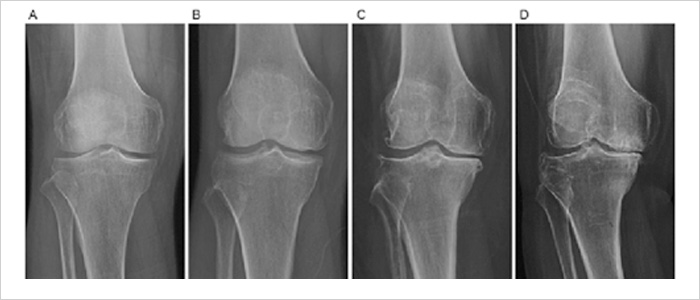

골 관절염 (퇴행성 관절염)은 켈그랜-로렌스 분류법으로 단계를 나누는데

4단계에서 보존적 치료가 반응을 안 할 시 인공관절 수술을 고려해야 합니다.